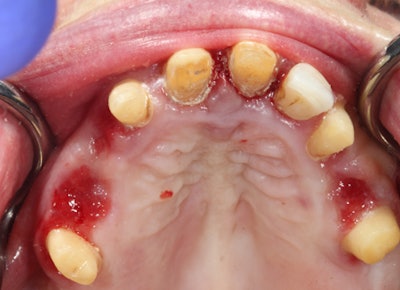

Flapless guided implant surgery only requires tissue punch to access the available bone (figures 3 and 4). When ample keratinized tissue is present and sufficient bone volume is present, sutures are unnecessary and the surgery is minimally invasive.

Figure 3: Workflow-guided implant.

The use of a guide will result in more accurately placed implants that can be easily restored with Cerec or conventional impression methods (figures 8-13 in slideshow below).

The guide safeguards the 3D position of the implant regarding depth, spatial relationship to the adjacent teeth, and proper angulation (figure 14). Practicing with these technologies will distinguish you from your colleagues.